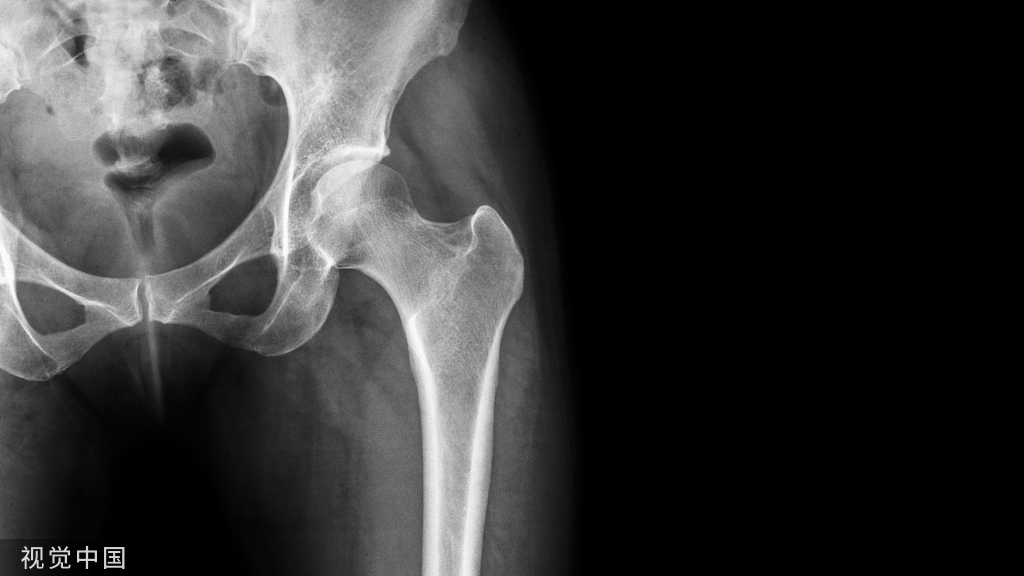

肩部正位平片显示锁骨中轴线状骨折,肩锁关节间隙无明显增宽,锁骨外侧端无明显增高